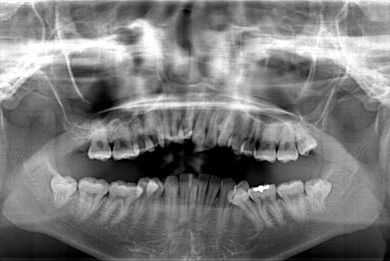

セラミック治療

| 性別/年齢 | 女性 / 20歳 | ||||||||||||||||||||||||||||||||

| 主訴 | 神経が死んで来ている歯が痛むので、治療をして欲しい。歯並びも良くできるのであればして欲しい。 | ||||||||||||||||||||||||||||||||

| 治療方針 | ジルコニアオールセラミック(クラウン1本、ブリッジ3本)、セラミック用土台2本 | ||||||||||||||||||||||||||||||||